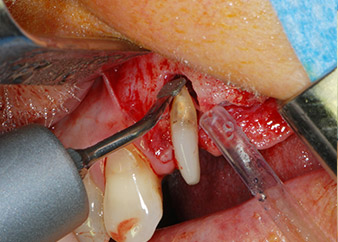

Un mes después, en el día de la intervención, el dolor y la inflamación se habían reducido al mínimo en la pieza 24, pero seguía habiendo una movilidad de clase II de Miller. Después de la apertura de los colgajos y de la limpieza del tejido infectado periapical y perirradicular, la extensión del defecto óseo quedó evidente (figuras 2 y 3).

En la raíz bucal, faltaba todo el hueso vestibular y distal. Básicamente, la fijación se limitó a la raíz palatal, lo que corroboró el mal pronóstico preliminar. La pieza 27 también mostró una fijación horizontal reducida (figura 12) y una rarefacción apical mínima (figura 1), si bien sin síntomas clínicos.

En primer lugar, en un intento por gestionar el problema endo-periodontal, el resto de la superficie radicular se desbridó con cuidado con un equipo piezoeléctrico (Piezomed de W&H, utilizado con el inserto S1 con forma de espátula, concebido en un principio para la erosión de la pared lateral del seno) (figura 4). A continuación, el ápice se erosionó con el mismo instrumento para eliminar el tejido apical infectado residual y reducir las posibles ramificaciones accesorias del canal radicular (apicectomía) (figura 5). No fue necesario realizar un retrorellleno, puesto que la obturación ortógrada se acababa de revisar.